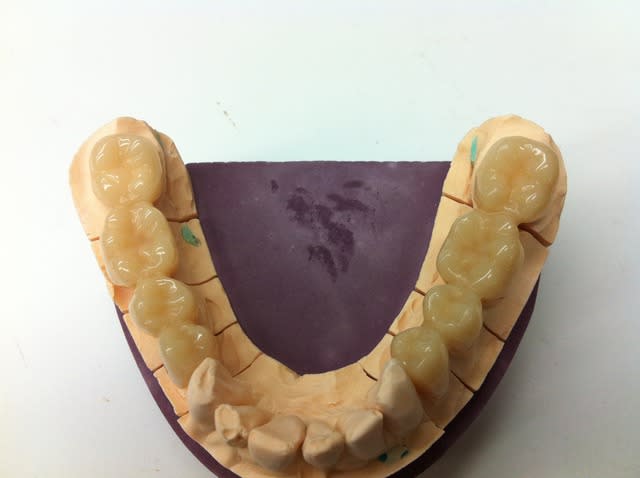

Voici les photos de la CAO, le soft m'a proposé un bridge décalé et en sous occlusion quoique bien fouillé comme expliqué précédemment,en le corrigeant j'ai perdu en anatomie mais gagné en équilibre et en solidité, j'aurai sans doute pu retravailler d'avantage les formes.

les connexions apparaissent en rouge et ont été étendues au maximum.

Voici encore des photos concernant l'intrados et la sculpture des faces occlusales nécessaire pour ce bridge.